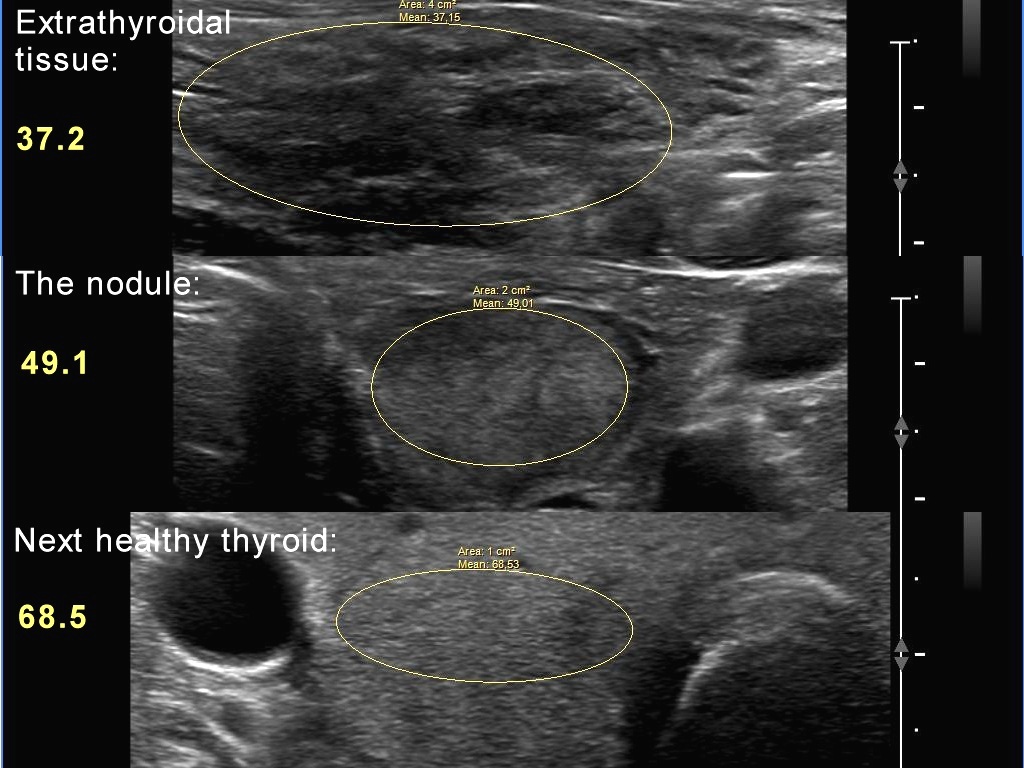

The echogenicity of the nodule - case 1177 (ultrasonographic picture 7)

Histogram analysis of the extranodular part (upper insert), the nodule (middle insert) and the next healthy thyroid on this day (lower insert) . The nodule is lighter than the extranodular part but darker than a healthy thyroid. So, it should be regarded as an iso/hyperechoic nodule or a hypoechoic nodule, reference tissue is the non-nodular part (all but the EU TIRADS) or normal, healthy thyroid (EU TIRADS).